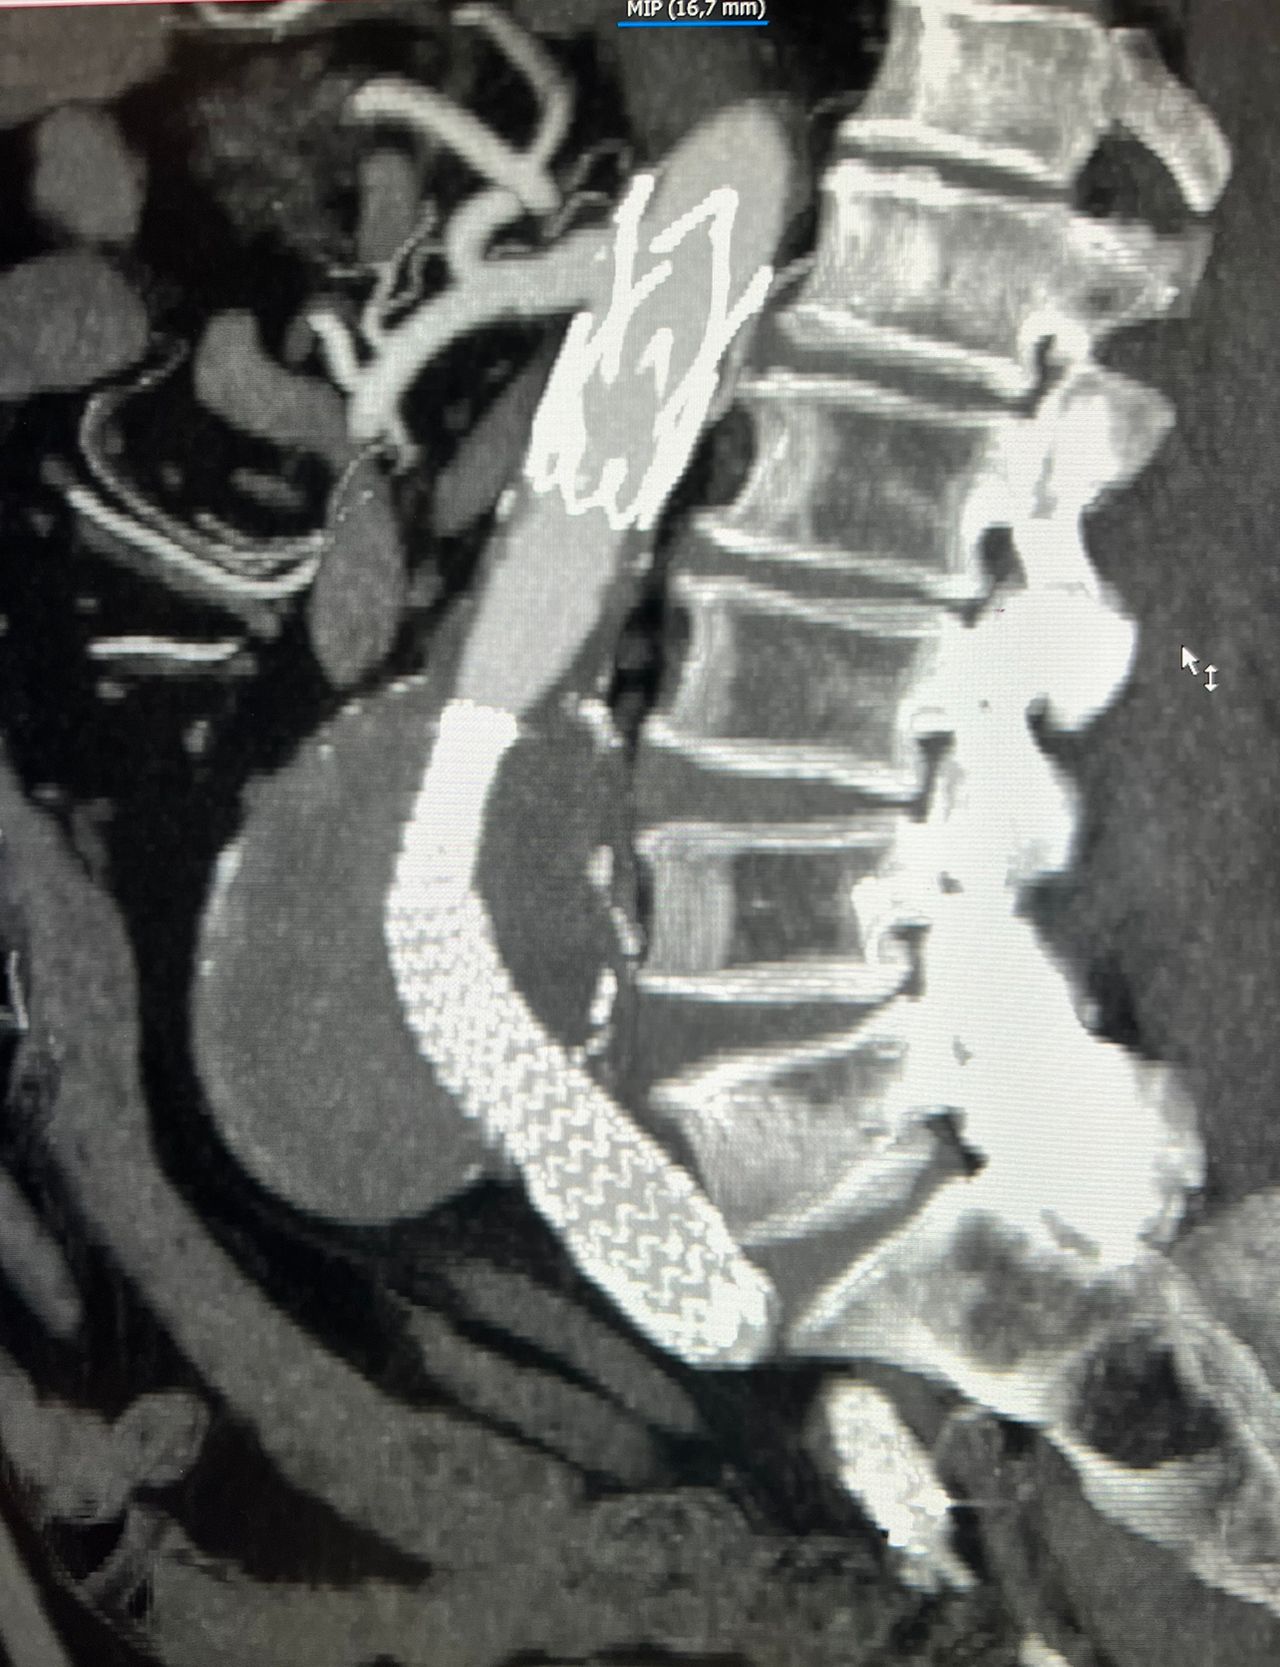

Foto e video